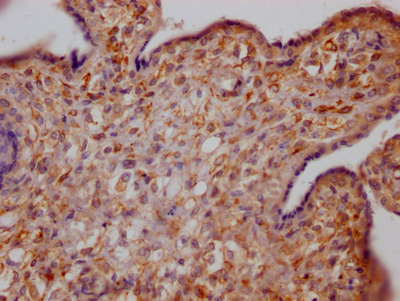

IHC image of CSB-RA978909A0HU diluted at 1:100 and staining in paraffin-embedded human placenta tissue performed on a Leica BondTM system. After dewaxing and hydration, antigen retrieval was mediated by high pressure in a citrate buffer (pH 6.0). Section was blocked with 10% normal goat serum 30min at RT. Then primary antibody (1% BSA) was incubated at 4℃ overnight. The primary is detected by a Goat anti-rabbit IgG polymer labeled by HRP and visualized using 0.05% DAB.

IHC image of CSB-RA978909A0HU diluted at 1:100 and staining in paraffin-embedded human liver tissue performed on a Leica BondTM system. After dewaxing and hydration, antigen retrieval was mediated by high pressure in a citrate buffer (pH 6.0). Section was blocked with 10% normal goat serum 30min at RT. Then primary antibody (1% BSA) was incubated at 4℃ overnight. The primary is detected by a Goat anti-rabbit IgG polymer labeled by HRP and visualized using 0.05% DAB.